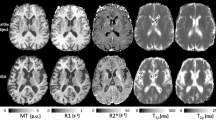

The magnitude images from the 10th echo, which was used for image registration, the echo-combined frequency shift map, the R2* map and the susceptibility map derived are shown in Fig. 1. The latter three images display better SNR as they were derived from data at different echo times. It is seen that all the images delineate white matter and grey matter, but the contrast is relatively weak on the magnitude and R2* images as compared to frequency shift and susceptibility maps. It is also seen that the boundaries of the deep nuclei regions are less definitive on the frequency shift maps as compared to the susceptibility maps due to the local dipole effects. These observations are consistent with previous reports. Also the R2* and susceptibility maps allow for direct quantification, as indicated by the scale bar. Illustrations of the ROI selections on white matter and grey matter for subject 1 are shown in Fig. 2, the actual ROIs were volumetric whereas only representative slices were shown.